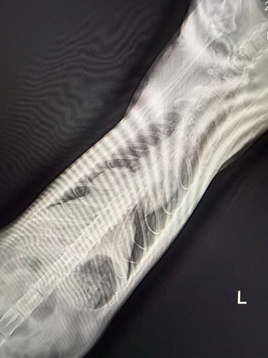

圖一| X光影像顯示腹腔器官異常移位至胸腔,肝臟位置明顯不正常。